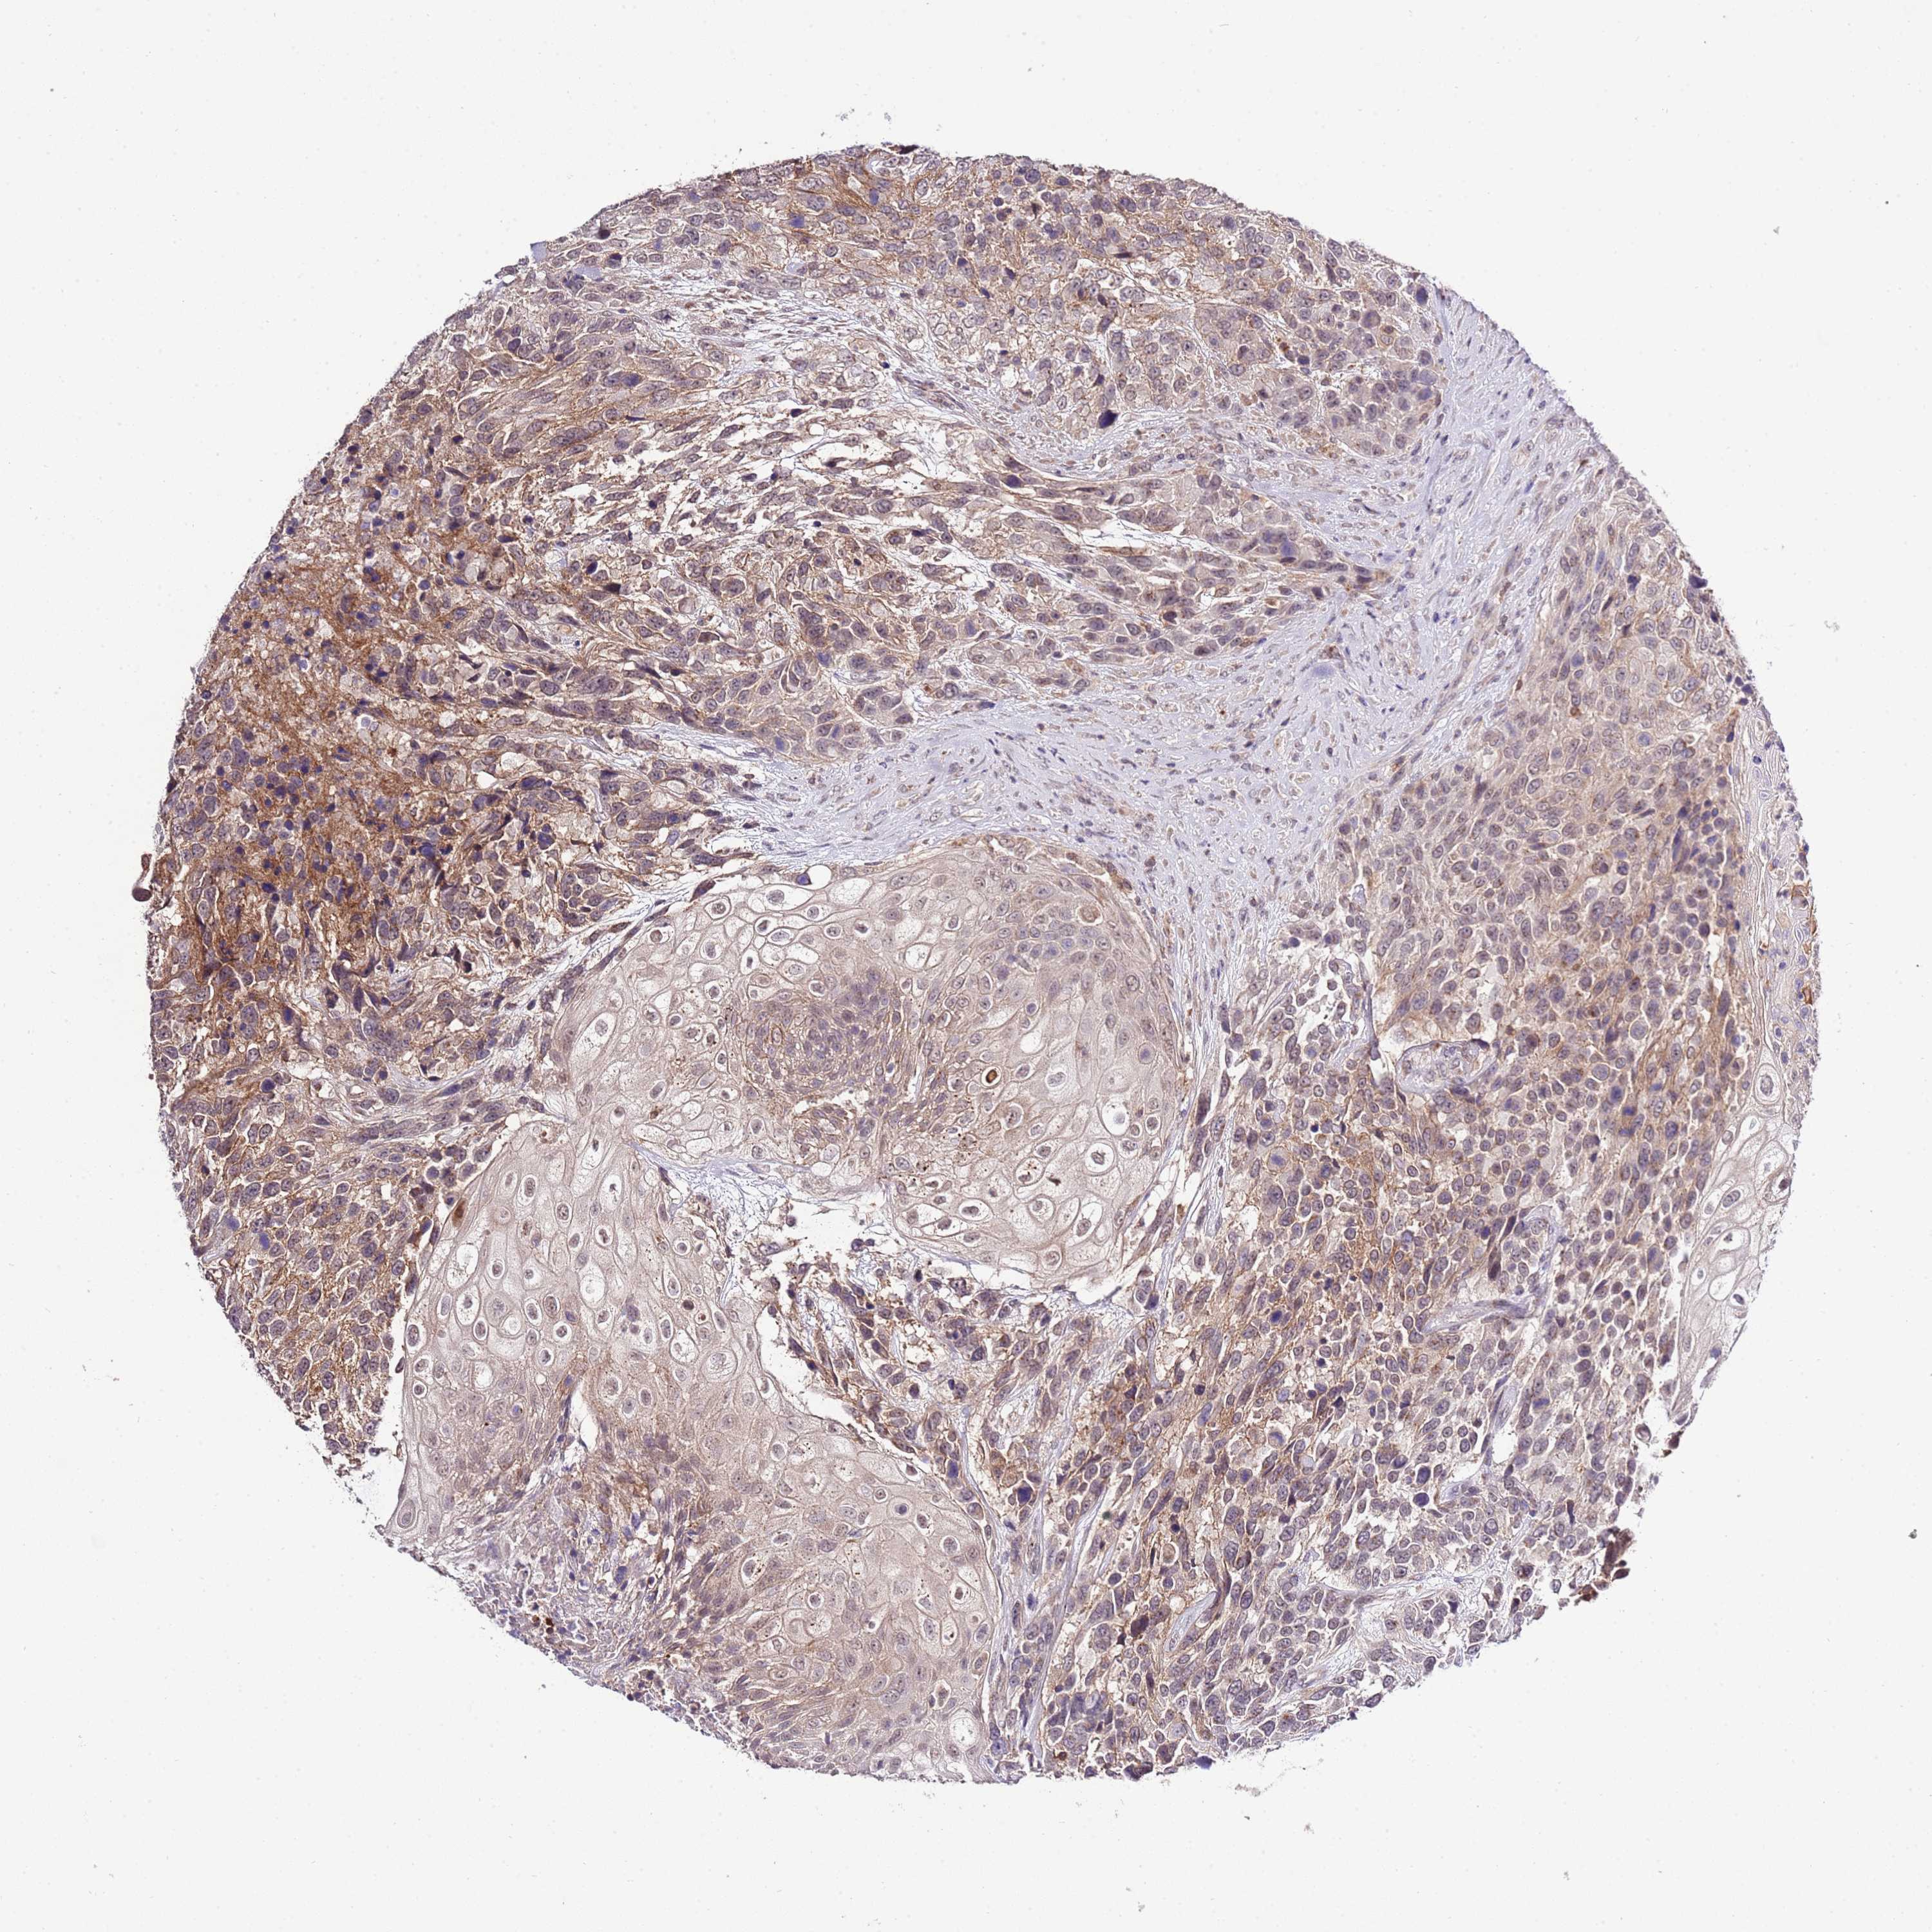

UROTHELIAL CANCER - Protein expressioni

A mouse-over function shows sample information and annotation data. Click on an image to view it in a full screen mode. Samples can be filtered based on level of antibody staining by selecting one or several of the following categories: high, medium, low and not detected. The assay and annotation is described here.

Note that samples used for immunohistochemistry by the Human Protein Atlas do not correspond to samples in the TCGA dataset.

Antibody stainingi

Antibody staining in the annotated cell types in the current human tissue is reported as not detected, low, medium, or high, based on conventional immunohistochemistry profiling in selected tissues. This score is based on the combination of the staining intensity and fraction of stained cells.

Each image is clickable and will lead to virtual microscopy that enables deeper exploration of all samples and also displays staining intensity scores, fraction scores and subcellular localization as well as patient and tissue information for each sample.

Antibody HPA049331

Antibody HPA056959

Urothelial carcinoma, Low grade

Urothelial carcinoma, High grade

Urothelial carcinoma, NOS